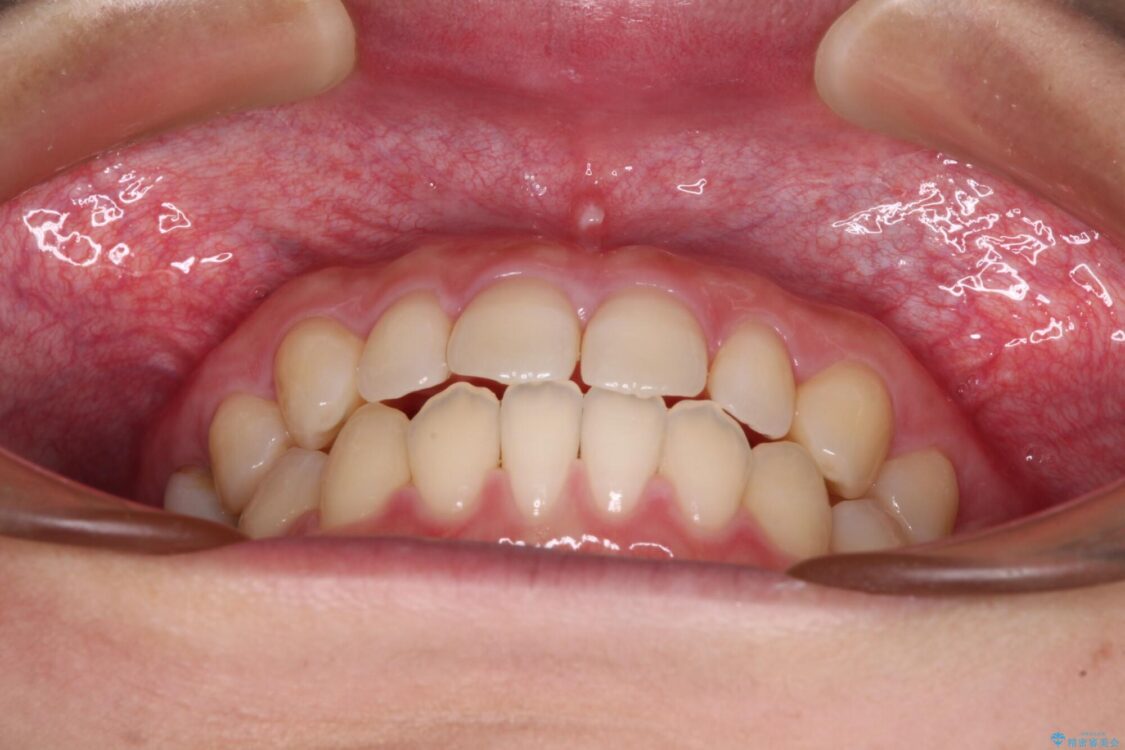

治療後

• 隙間だらけの歯列 インビザラインで改善 治療後画像